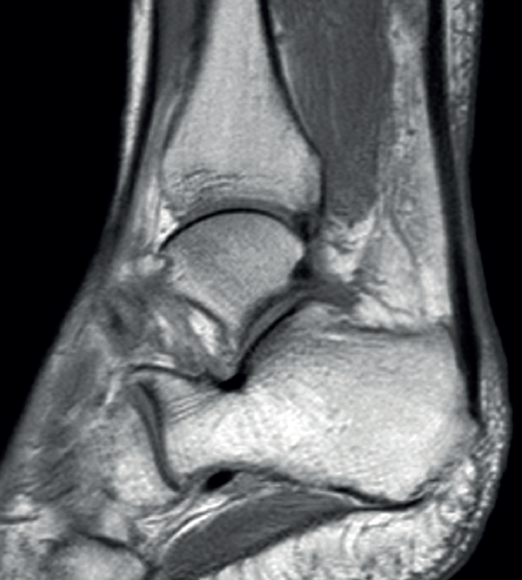

The normal Achilles tendon is observed as a hypointense structure in both T1- and T2-weighted sequences(33) (Figure 3). In the sagittal plane its margins are parallel, and in the axial plane its distal portion presents an anterior concave margin towards the calcaneus over most of its course. The thickness is similar along its trajectory, and a minimum amount of fluid is observed at retrocalcaneal level (fluid surrounding the tendon is pathological)(34).

Figure 3. Magnetic resonance imaging view of ankle (T1 sequencing). Sagittal view showing a normal tendon.